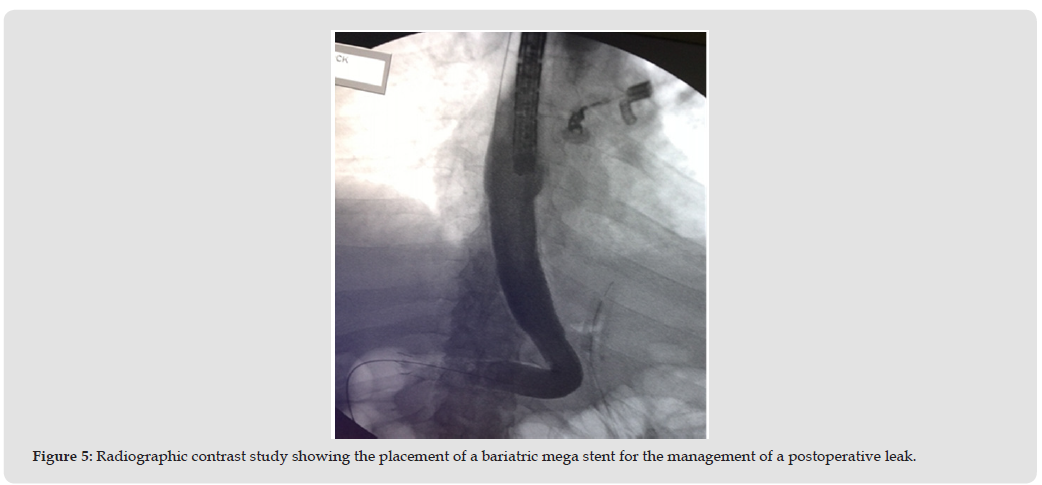

A narrative review of major series and meta-analyses on SEMS for post-bariatric surgery leaks was conducted. Studies included data on SG and RYGB leaks, success rates, complications, and comparisons with other techniques. Meta-analyses, including more than 400 patients have consistently demonstrated closure rates of approximately 90% in acute cases. Customized bariatric stents have been evaluated in several studies, with reported success rates up to 100%, but their use is limited by higher complication and migration rates.

The efficacy of SEMS in the management of post-bariatric leaks is well documented. Pooled analyses demonstrate overall success rates ranging from 72% to 93%. Success is significantly higher in acute and early leaks (less than 6 weeks post-surgery), whereas chronic leaks respond poorly, with markedly lower closure rates. Closure rates appear similar between sleeve gastrectomy (92%) and Roux-en-Y gastric bypass (96%). Complications remain a concern. Migration occurs in 15–32% of cases, particularly with bariatric-specific stents. Adverse events include abdominal pain, reflux, nausea, ulceration, bleeding, and stricture formation (8–13% with bariatric SEMS). Strategies to reduce migration include endoscopic fixation with suturing or clips, or the use of partially covered SEMS. When compared with alternative therapies, SEMS show strengths and limitations. Endoscopic vacuum therapy (EVT) and endoscopic internal drainage (EID) have demonstrated high success rates in chronic leaks and fistulas, often outperforming SEMS in these contexts. Over-the-scope clips (OTSC) are effective for small defects or in combination with SEMS. Cost-effectiveness analyses indicate that double-pigtail stents or EID may provide similar closure rates at lower costs. Combination approaches, such as SEMS with double-pigtail stents or SEMS with OTSC, appear to improve overall outcomes and reduce recurrence.

The role of SEMS in the management of post-bariatric leaks is evolving. SEMS provide immediate coverage of large defects and allow for early resumption of enteral nutrition, which is critical in unstable or malnourished patients. Their utility is greatest in acute settings, where rapid control of sepsis and leak closure is required. Nevertheless, limitations exist. Migration rates remain high despite design improvements, and stent intolerance frequently necessitates early removal. Customized bariatric stents, although anatomically suitable, may paradoxically increase migration and stricture rates. Recent advances such as EVT and EID have broadened the therapeutic landscape, particularly for subacute and chronic leaks, where SEMS is less effective. Increasingly, a multimodal strategy is adopted, combining SEMS with internal drainage or clips to enhance success and minimize complications. Importantly, management should be individualized, considering defect size, chronicity, patient condition, and institutional expertise. Endoscopic treatment should occur within a multidisciplinary framework, involving surgeons, interventional radiologists, and intensivists.

SEMS remains an important tool in the endoscopic treatment of post-bariatric leaks, particularly in acute and early cases. They provide rapid control, facilitate nutrition, and can be combined with complementary therapies. However, their role in chronic or complex leaks is diminishing in favor of EVT, EID, or multimodal approaches. The optimal strategy is stepwise, patient-centered, and guided by a multidisciplinary team [1-9] (Figures 1- 5).